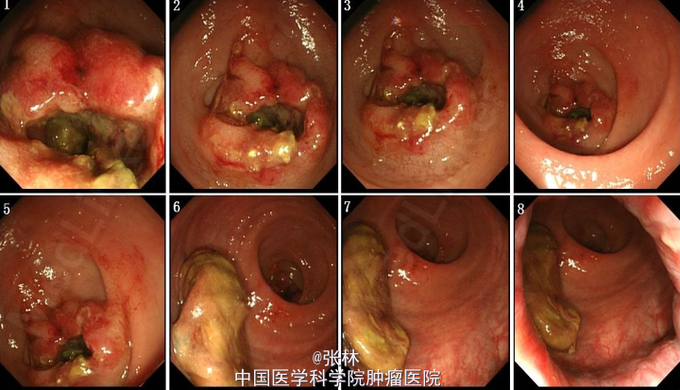

直肠癌T3N1c一例

肠镜;直肠距肛门9cm处全周菜花样肿物生长,管腔狭窄,内镜不能通过,肿物处取活检5块。 病理:浸润性中分化腺癌(至少粘膜内腺癌,取材表浅) 钡灌肠:上段直肠有一长约4.1cm不规则充盈缺损、粘膜破坏,管腔狭窄 CT:1、乙状结肠及部分直肠肠壁增厚,累及周围脂肪间隙,请结合镜检。 2、肝脏多发结节,倾向囊肿。

行腹腔镜辅助直肠癌前切除术。探查:无腹水,肝胆脾胰腺等腹盆腔脏器未见肿瘤转移,肿瘤位于腹膜反折处,侵及浆膜,近端肠管水肿,肠壁增厚。 术后病理:(直肠癌根治标本) 直肠浸润溃疡型中分化腺癌,肿物大小4.5×2×0.5cm,累及肠周脂肪组织。可见神经侵犯,未见明确脉管瘤栓。上切缘、(2)(下切缘)及环周切缘均未见癌。 淋巴结未见转移性癌(0/41).pTNM分期:pT3N1c

病例特点:老年男性,低位直肠癌;行Dixon术,术后病理pT3N1c。患者术后病理未见转移性淋巴结,但是肠壁周围发现一枚癌结节,在最新的nccn分期上面,癌结节归类为N1c分期,因此该患者是分到了三期,需要仅行术后辅助治疗。